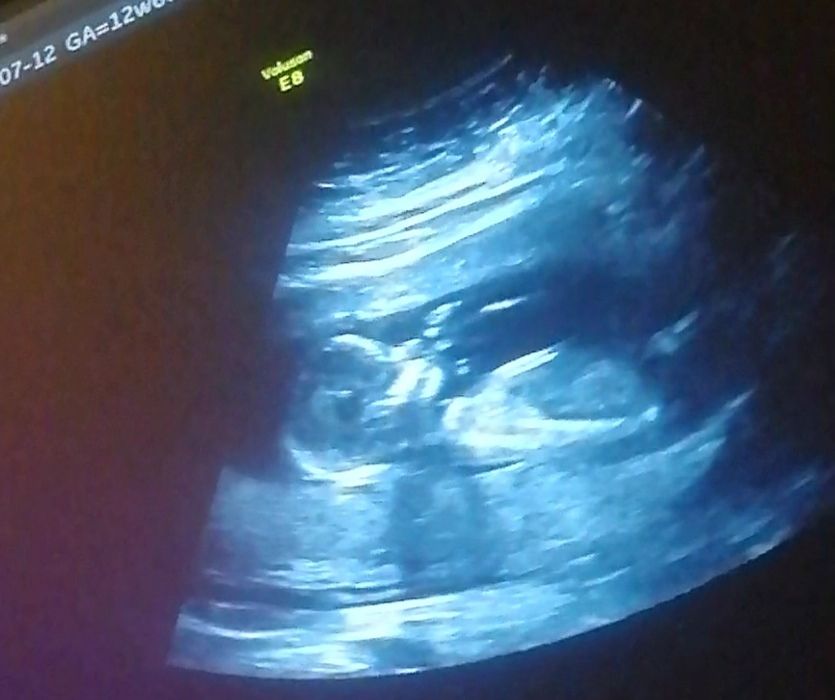

вот наш 1 скрининг в 12+5 с дочей )